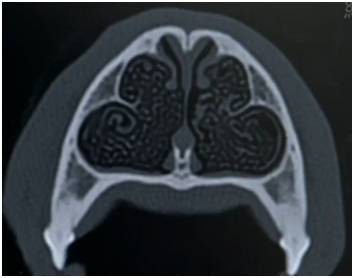

狗狗鼻腔内有呈涡旋状的

鼻甲骨

,上面被覆有嗅上皮细胞,汪星人鼻腔内的这种涡旋状结构展开可以达90平方厘米,有约1.5亿个嗅觉受体,不同品种会有差异,比如腊肠犬有1.25亿个嗅觉受体,寻血猎犬有3亿个嗅觉受体!